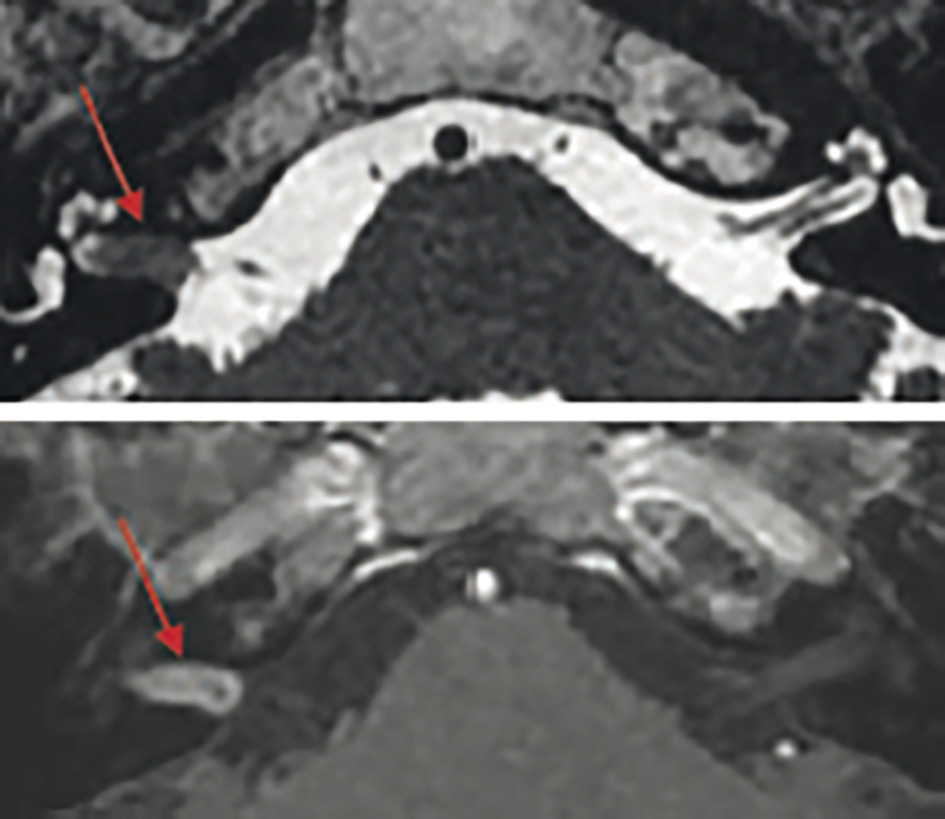

Siège volontiers dans le conduit auditif interne et croît vers l’angle ponto-cérébelleux (APC). D’où atteinte des fonctions vestibulaires et auditives.

L’IRM a amélioré la détection des schwannomes de petite taille (70 % des cas au diagnostic).

Examen le plus sensible pour apprécier la stabilité ou l’évolution de la tumeur.

Tumeurs de petite taille au retentissement fonctionnel modéré.2 C’est le cas des petites lésions (intracanalaires pures ou < 15 mm de diamètre dans l’APC) en première intention, sauf chez les sujets jeunes avec une audition inutile (restes auditifs trop faibles pour être amplifiés par une aide) ou si tentative de préservation de ce sens.

Au cours de la surveillance des tumeurs intracanalaires et de celles de moins de 15 mm, la croissance moyenne est d’environ 1 mm par an et la dégradation de l’audition de 4 à 5 dB par an (vs 5 dB/10 ans si presbyacousie).3 De plus, le risque de croissance rapide dans 20 % des cas justifie une IRM précoce à 6 mois puis avec une fréquence annuelle.